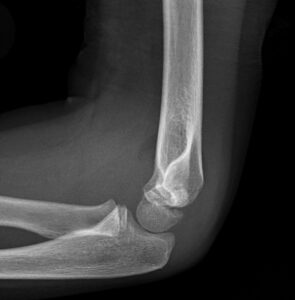

[toggle title=”Suprakondiler Humerus Kırığı” state=”close”]

Tüm dirsek bölgesi kırıklarının %60-70ini suprakondiler humerus kırıkları oluşturur.

En sık 5-8 yaş arasında görülür ve erkek: kız oranı 3:2’dir

Ekstansiyon tipi yaralanma (%95) çoğunlukla açık el üzerine düşme sonrası görülürken, fleksiyon tipi yaralanma (%5) daha çok dirseğin direkt travmaları sonrası görülür

Kırıklar Gartland sınıflaması ile sınıflandırılır.

Tip 1: Ayrışmamış kırıklardır ve grafide belirlenmesi zor olabilir.

Tip 2: Arka korteksin sağlam olduğu deplase kırıklardır. Anterior Humeral Hat kapitellumu kesmez, önünden geçer.

Tip 3: Ön ve arka kortekste belirgin ayrılma vardır. Tam deplase kırık.

Tip 4. Fleksiyon ve ekstansiyonda instabil olan kırıklardır